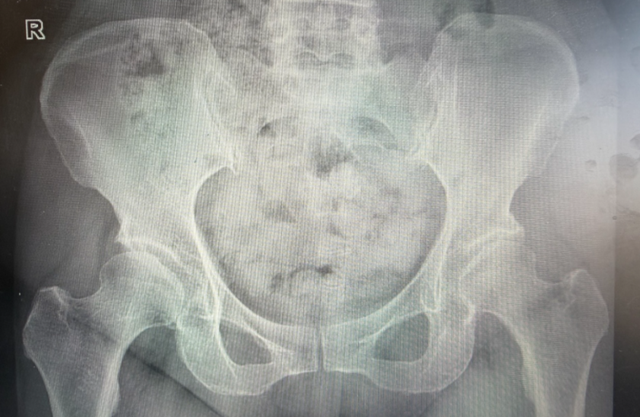

经过详细病史询问、体格检查及影像学评估(MRI),医生找到问题所在:双侧髋臼发育不良(髋臼覆盖不足,容易导致关节不稳定),髋关节退行性变(软骨磨损、骨髓水肿、囊变形成),股骨大转子滑囊炎(炎症导致疼痛),髋关节积液(关节内炎症反应)。

结合临床表现,李女士被诊断为双髋关节撞击综合征(FAI)。这是一种由于髋关节结构异常(如髋臼或股骨头形态异常)导致关节活动时异常摩擦,进而引发疼痛、盂唇损伤甚至骨关节炎的疾病。